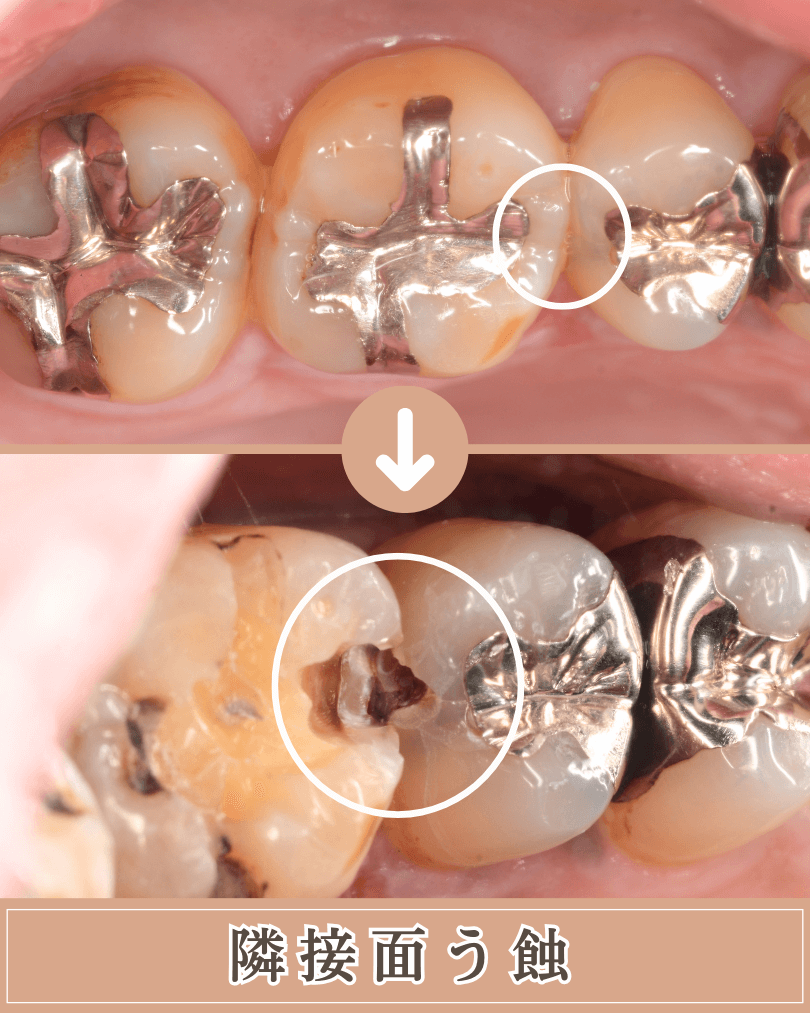

隣接面(歯と歯の間)

歯と歯が隣り合っている面(隣接面も、虫歯ができやすい場所として、知られています。

隣接面も、歯ブラシの毛先が届きにくい場所で、お口の中でも特に汚れがたまりやすく、虫歯が発生しやすいという場所です。

この虫歯の怖いところは「特に発見しにくいこと」にあります。

歯と歯の間ですから自身では見つけにくく、歯科医師でも肉眼では発見できないことが多いです。

レントゲン写真で見つかる事も多いですが、それでもうまく隠れてしまい100%発見できるとは限りません。

定期メンテナンスに通われている方は、外観からの微妙な違和感や、歯石除去時のひっかかりなどから、比較的早い段階で見つかる事が多いです。